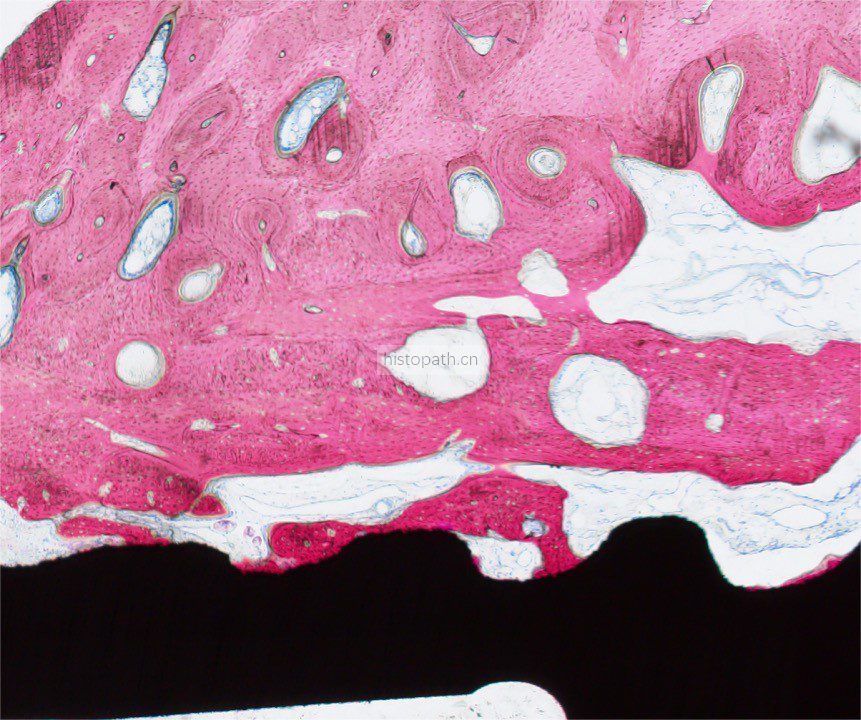

将包埋好的硬组织树脂块,用EXAKT 硬组织切片机先切一个200um的厚片,然后再通过EXAKT 硬组织磨片机将其磨到20-30um薄片,样本是已经硬组织包埋好的含金属的动物样本。

具体步骤:包埋块修开切面抛光-平行粘片装置粘片-硬组织切片机切片-硬组织磨片机磨片抛光成片。

针对不同的病理阅片指标需求,行HE染色、Masson染色、亚甲基蓝-酸性品红染色、VG染色、Movat染色等。